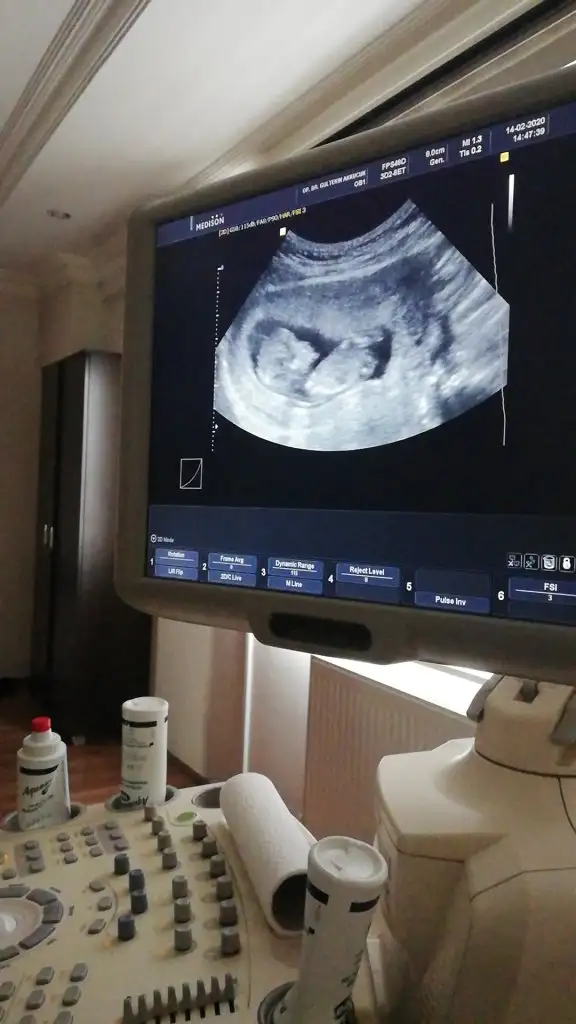

Bacak arası nubuda dik görünüyor erkek 11+2 dimi usg 12+ yada 13 olursa paylaşın A Aryaam

Bir de bunlara bakın isterseniz